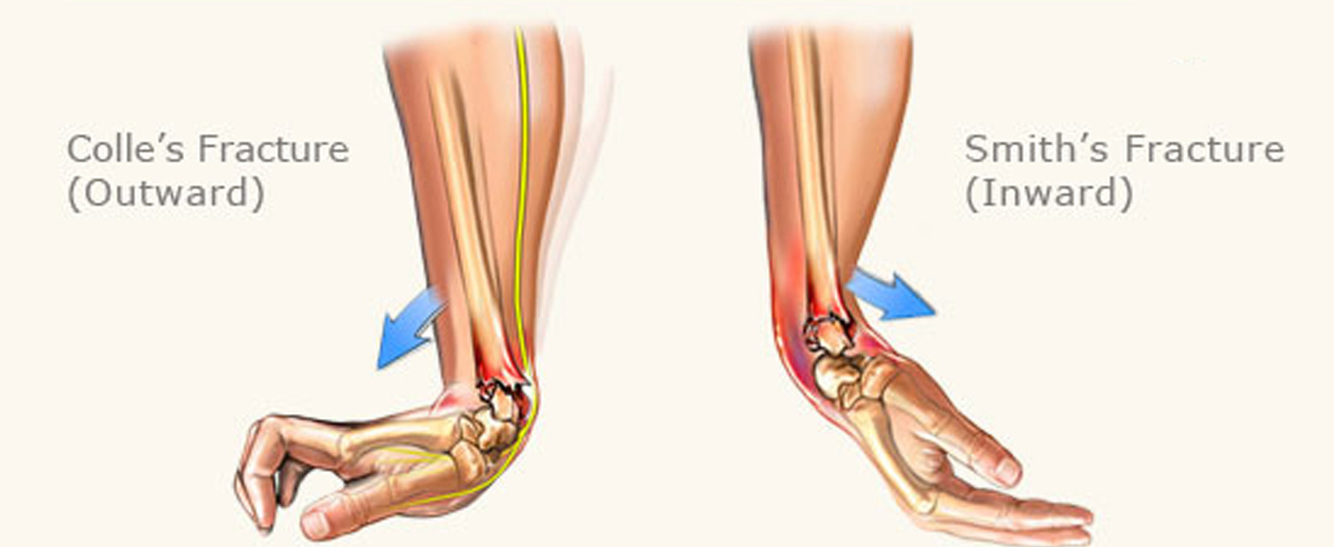

What is a Colles’ fracture?

An extra articular fracture of the distal radius within an inch of the articular surface and with dorsal displacement or angulation

What is a Smith’s fracture?

A volarly displaced or angulated extra-articular fracture of the distal radius

How is a Smith’s fracture commonly sustained?

Falling onto the back of a flexed wrist

A _________ fracture involves a volarly displaced distal radius, whereas a _________ involves a dorsally displaced distal radius

A Smith’s fracture involves a volarly displaced distal radius, whereas a Colles’ involves a dorsally displaced distal radius